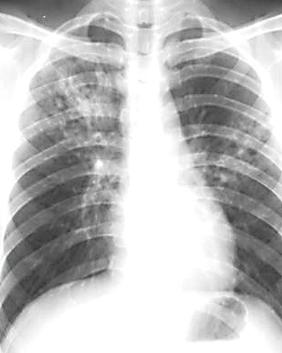

肺结核是由结核分枝杆菌引发的肺部感染性疾病,可侵及许多脏器,以肺部结核感染最为常见。排菌者为其重要的传染源。人体感染结核菌后不一定发病,当抵抗力降低或细胞介导的变态反应增高时,才可能引起临床发病。若能及时诊断,并予合理治疗,大多可获临床痊愈。肺结核是严重威胁人类健康的疾病。

胸片结果:两肺门散在斑点状钙化,考虑陈旧性肺结核钙化所致